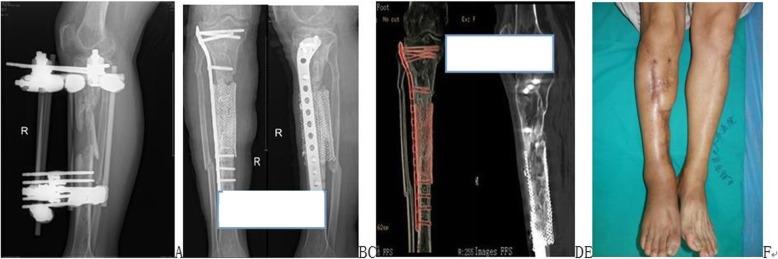

Management of large segmental tibial defects using locking IM nail and absorbable mesh.

BMJ Case Rep. 2013 Jul 25;2013:bcr2013010480. doi: 10.1136/bcr-2013-010480.

Two-stage reconstruction of post-traumatic segmental tibia bone loss with nailing.

Orthop Traumatol Surg Res. 2010 Sep;96(5):549-53. doi: 10.1016/j.otsr.2010.02.010. Epub 2010 Jun 4.

Treatment of large segmental bone defects with reamer-irrigator-aspirator bone graft: technique and case series.

Orthop Clin North Am. 2010 Jan;41(1):63-73; table of contents. doi: 10.1016/j.ocl.2009.08.002.

Treating segmental bone defects: a new technique.

J Foot Ankle Surg. 2008 Jul-Aug;47(4):350-6. doi: 10.1053/j.jfas.2008.04.006.